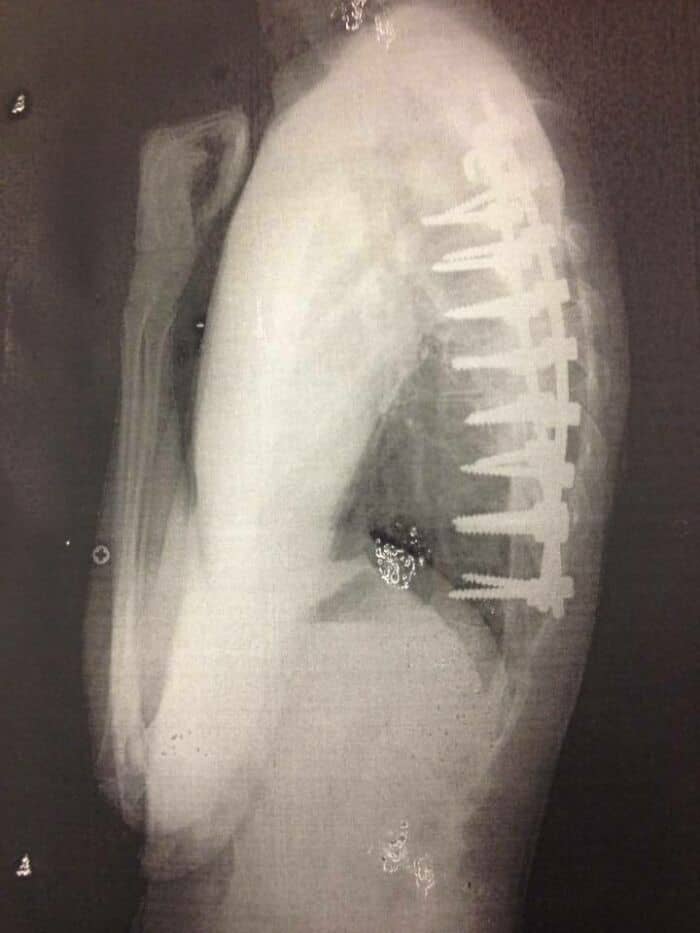

#22 In My Head, The Screws From My Spinal Fusion Surgery Looked A Lot Smaller